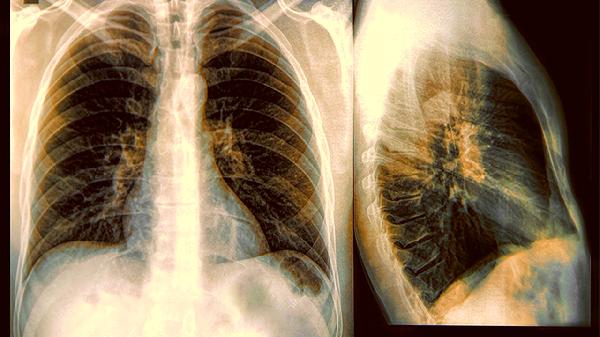

那种叫"小细胞肺癌"的家伙,十个患者里有九个半是老烟民。这种癌细胞跑得特别快,往往刚发现就悄悄转移了,医生手里的治疗武器也比其他肺癌少得多。